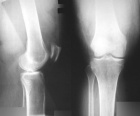

44 year old woman with a few years of left knee pain now with increasing pain and left thigh mass first noticed a few months prior to presentation

Zoom image: Radiological image Radiological image.